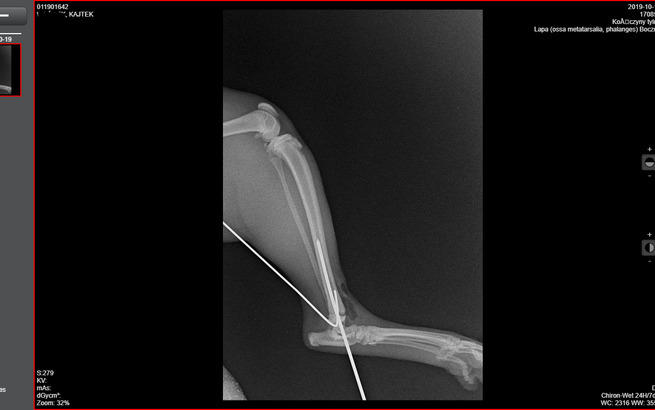

Zbieramy fundusze na operację Kajtka.

Kajtek nie miał łatwego życia. Znaleźliśmy go w pudle. Był w dramatycznym stanie. Najmniejszy i najsłabszy że stada... a mimo to najbardziej się łasił i lgnął do człowieka. Przez koci katar pękło i wypłynęło mu oczko. Wymagał opieki, zakraplania, masowania. Postanowiliśmy, że zostanie u nas, w domu tymczasowym, na stałe. Kiedy podrósł wymagał dwóch operacji: oka oraz migrującego jądra. Przeszedł je całkiem niedawno. Teraz znów uległ wypadkowi...

Koszt to 1500zł + wizyty, leki, pobyt w klinice, badania i prześwietlenia... My prosimy chociaż o 500. Wiemy, że siła tkwi w dobrych ludziach.